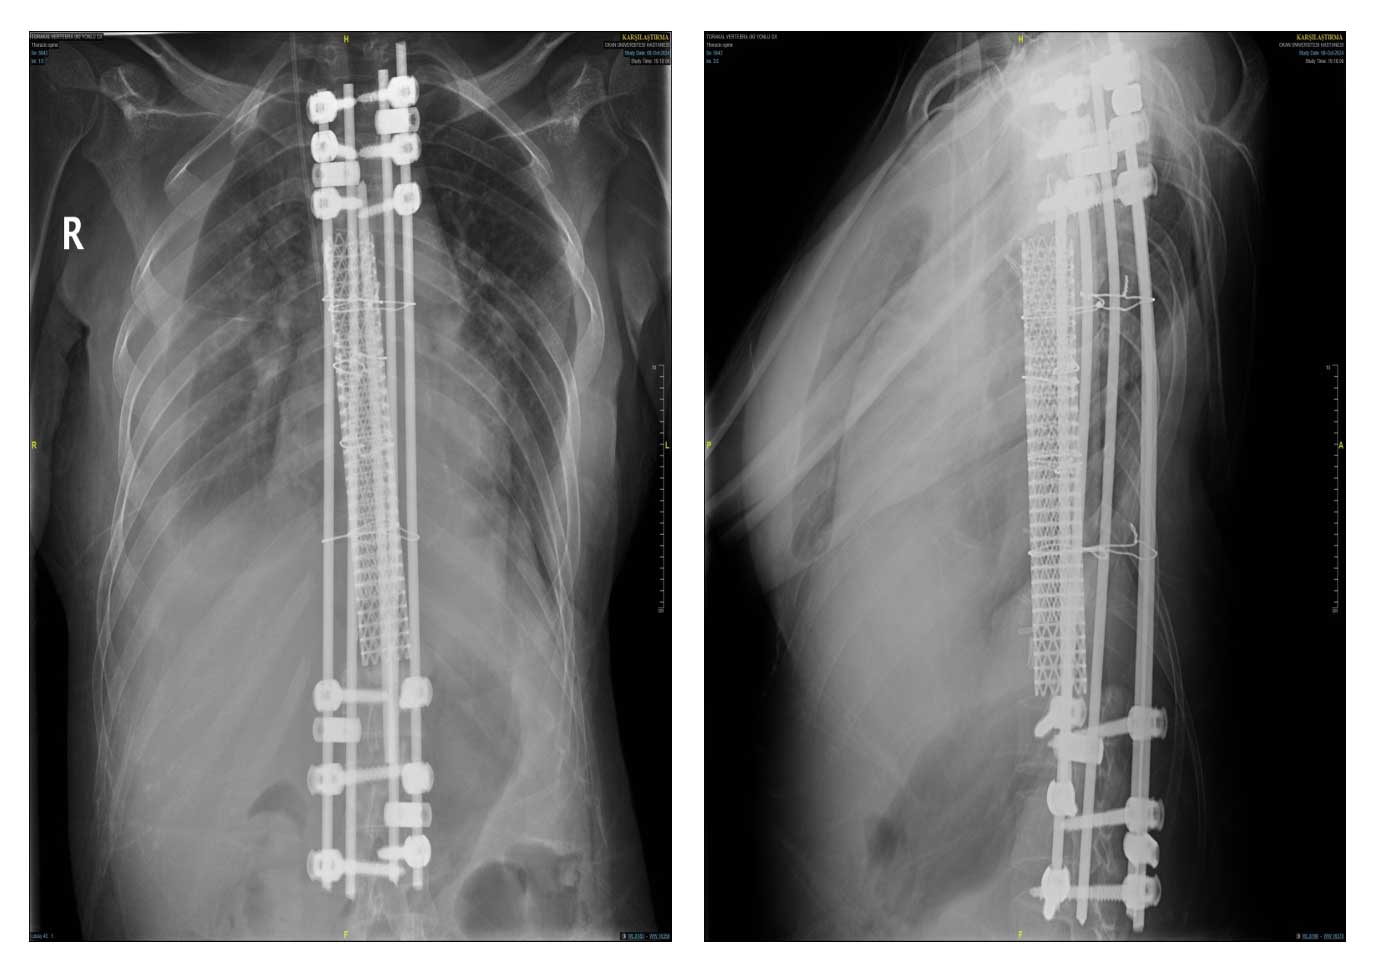

Ameliyat Sonrası: Röntgende korpektomi sonrası fibula, cage ve enstrümentasyon uygulaması görülmekte.